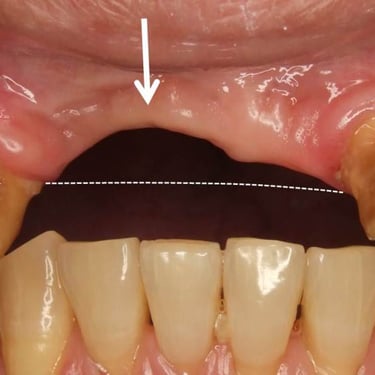

Pérdida de un diente único

La pérdida de un diente único es cuando un solo diente se ha caído o ha sido extraído, y se necesita un implante para reemplazarlo.

Los pacientes pueden notar un espacio donde solía estar el diente. Esta condición puede afectar la estética y la función masticatoria.

El tratamiento incluye la colocación de un implante dental para restaurar el diente perdido.